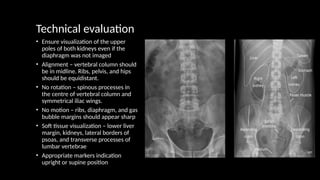

Technical evaluation

• Ensure visualization of the upper

poles of both kidneys even if the

diaphragm was not imaged

• Alignment – vertebral column should

be in midline. Ribs, pelvis, and hips

should be equidistant.

• No rotation – spinous processes in

the centre of vertebral column and

symmetrical iliac wings.

• No motion – ribs, diaphragm, and gas

bubble margins should appear sharp

• Soft tissue visualization – lower liver

margin, kidneys, lateral borders of

psoas, and transverse processes of

lumbar vertebrae

• Appropriate markers indication

upright or supine position